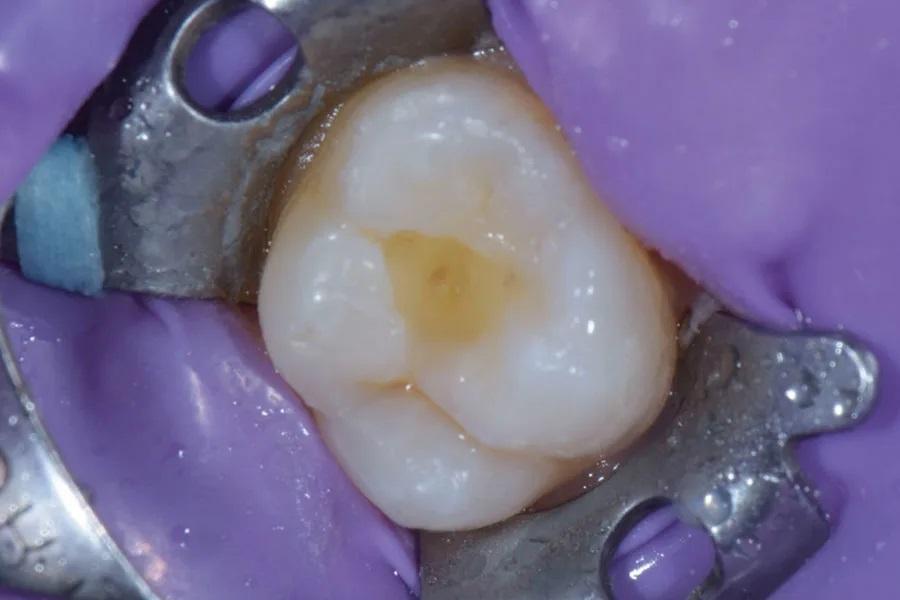

После анестезии зуб 2.6 изолирован коффердамом и частично рассверленным клампом (Фото 2). На всю поверхность непредпрепарированного зуба 2.6 нанесен тонкий слой разделительного агента — вазелина — микрокистью (Micro Applicator, Ultradent). Для изготовления окклюзионного индекса на поверхность зуба нанесен текучий композит для объемного внесения (Admira Fusion x-base, VOCO) (Фото 3). Микрокистью с легким давлением зафиксированы окклюзионные особенности и топография, создав необходимые детали на «штампе». Композит засвечен 20 секунд (Bluephase, Ivoclar); стержень микрокисти внедрен в композит, но не касается анатомии зуба.

Фото 2. Зуб 2.6 изолирован.

Фото 3. После нанесения разделительного средства на непрепарированный зуб 2.6 на поверхность зуба наносили текучий композит и подвергали светоотверждению.